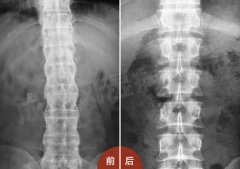

• 强直性脊柱炎竟是不良姿势惹的祸

年仅15岁的沈先生却患有强直性脊柱炎三年,出现驼背现象,无法正 ...